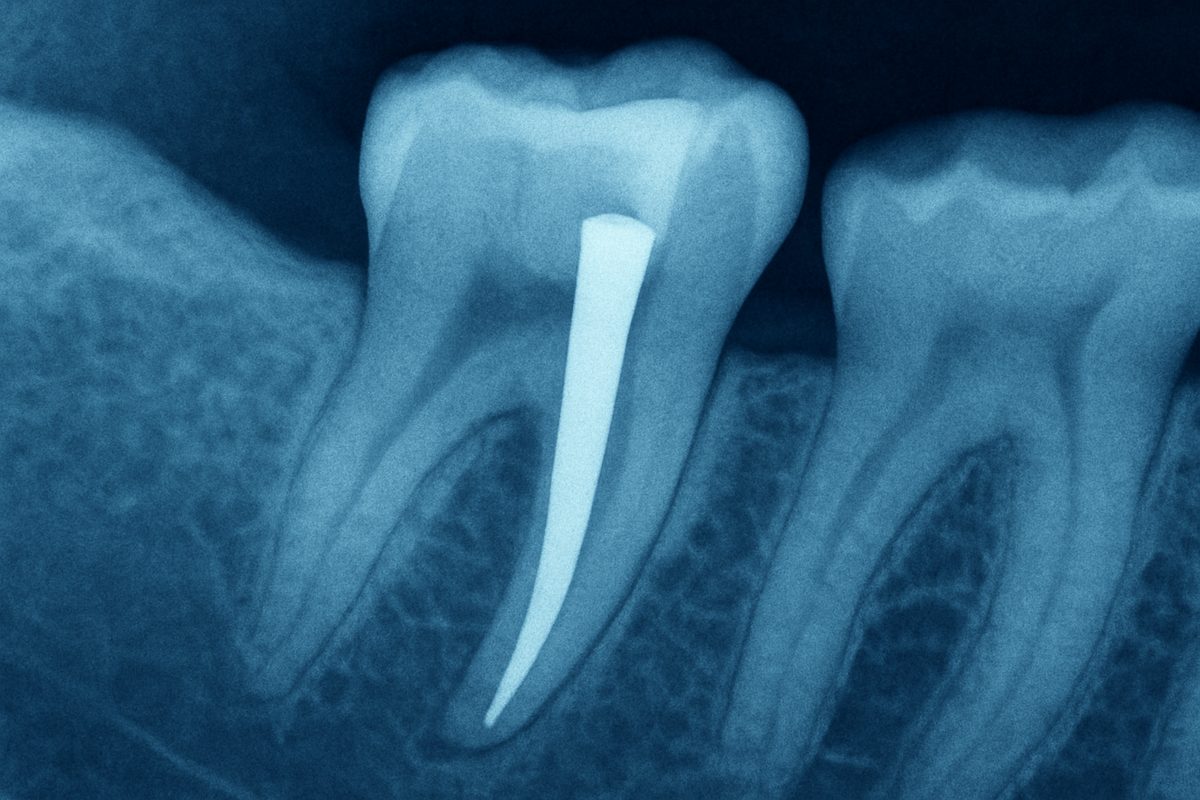

Initial exam and imaging

Placement starts with an exam and X-rays or CBCT scans to check root health and bone. Imaging shows root shape, length, and any signs of infection. Good imaging helps avoid complications before making space for a post.

A tooth with post is a natural tooth that had a root canal and then received a post inside the root. The post helps hold a core buildup and the final crown when there isn’t enough natural tooth structure left. The post does not replace the root; it reinforces the tooth so the crown can stay secure.